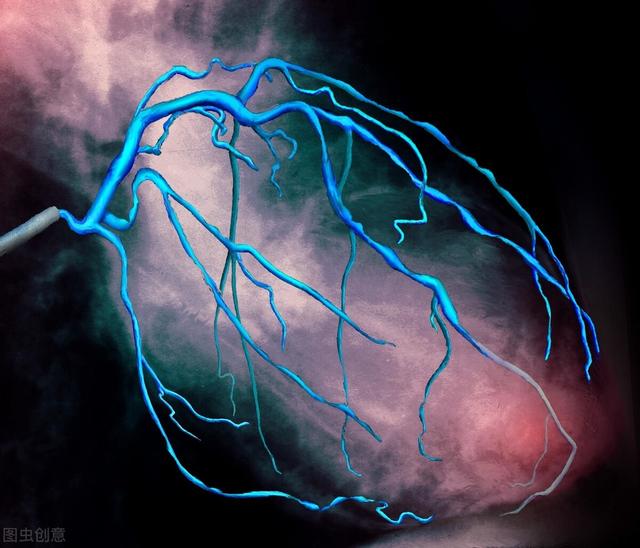

以上のようにして、左冠動脈または右冠動脈の主動脈とその分枝の内腔を明瞭に可視化し、冠動脈系の血管に狭窄病巣が存在するかどうか、また狭窄の程度を確認することができる。その後、治療計画を決定することができる。例えば、外科的バイパス術を行うか、保存的内科的治療を行うか。あるいは全く治療を行わないこともある。

(2)具体的な手順:患者は心臓カテーテル検査室の手術用ベッドに横たわり、手術部位を消毒し(手または大腿部)、この部位に局所麻酔薬を投与し、動脈血管に針で穴を開け、細いガイドワイヤーとカテーテルを送り、X線の監視下で血管をたどって冠動脈までガイドワイヤーカテーテルを到達させ、細いカテーテルの頭部に一種の薬(造影剤)を注入することで、X線の下に血管が映し出され、血管の大きさ、進み方、閉塞の有無、左冠動脈、右冠動脈、各枝などが一目でわかる。X線の下に血管が映し出され、血管の大きさ、進み方、詰まりの有無、左右の冠動脈、各枝などが一目でわかる。問題が深刻でなければこれで終わりで、カテーテルを抜き、出血を防ぐために手首の穿刺部をコンプレッサーで圧迫する。熟練していれば、全行程で10~30分かかる。問題が深刻な場合は、治療(バルーン拡張術、ステント留置術など)が続き、時間がかかることがあります。